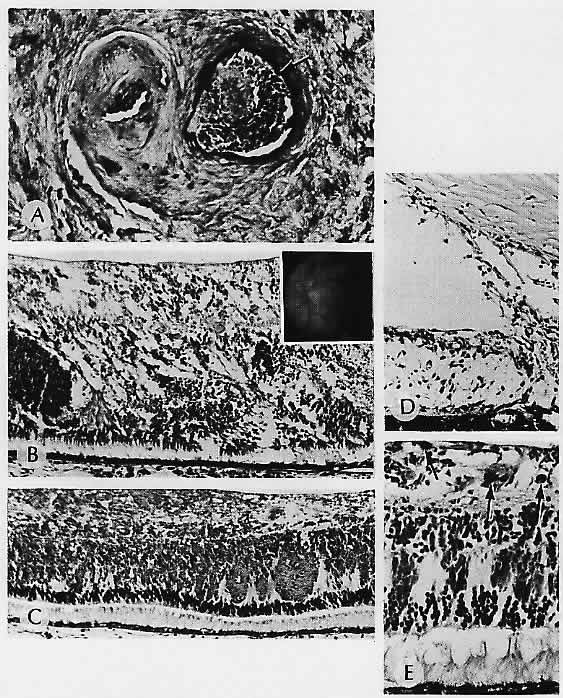

Histologically, increased basophilia of Bruch's membrane is seen, indicating both calcification and also a progressive increase in lipid deposition (Fig. 19).101 With increased age, wide-banded (“100 nm”) collagen is also deposited in Bruch's membrane, not only between the retinal pigment epithelium and its basement membrane but also in the two collagenous zones of Bruch's membrane and between the outer collagenous zone and the basement membrane of endothelium of the choriocapillaris. Sarks102 found that the wide-banded collagen was most abundant between the infoldings of the retinal pigment epithelium plasma membrane and its basement membrane and called it a “basal laminar deposit.” Green and co-workers103 found this material most frequently within the inner aspect of Bruch's membrane and called it “diffuse drusen.” Wide-banded collagen deposition may be considered a nonspecific aging change.

Fig. 19. Senile macular degeneration. A. Basophilia of the region of Bruch's membrane (arrows) is a common senile change. Note the partial obliteration of the choriocapillaris. Such aging changes may be precursors of some senile degenerations in the macular region. B and C. Fragile basophilic Bruch's membrane, which shows numerous cracks. B. Positive result (arrows) with a special stain to demonstrate the presence of calcium. D. Electron micrograph shows dark areas representing calcification in the region of Bruch's membrane. (A, H&E, ×395; B, von Kossa, ×252; C, H&E, ×252; D, ×20,000)

Drusen

Drusen (German, “bumps” or “bodies”) are the initial clinical findings in age-related macular degeneration. Typical hard (hyaline) drusen contain complex lipids, which are undigestible end-products of outer segment digestion by the retinal pigment epithelium. By themselves, they do not cause visual loss, and many persons who have drusen never show other changes of macular degeneration.102 In an autopsy series of patients 36 to 94 years of age, no increase occurred in the number of drusen with advancing age.

The retinal pigment epithelium is intact but thinned overlying the drusen, so they may appear as window defects on fluorescein angiography, showing early hyperfluorescence and staining but no leakage. Not all drusen can be seen clinically. Very small ones have been identified in postmortem eyes by scanning electron microscopy that could not be seen clinically or grossly.106

Histologically, hard drusen are dense, rounded, homogeneous bodies beneath the basement membrane of the retinal pigment epithelium. They have a uniform consistency, are periodic acid-Schiff positive, and contain lipid. Ultrastructurally, they contain finely granular material, vesicles, and sometimes wide-banded collagen. They may represent focal metabolic abnormalities of the retinal pigment epithelium.103

Several theories exist to explain the formation of hard drusen. Some histologic evidence supports the theory of Burns and Feeney-Burns that they are formed from shedding of portions of the retinal pigment epithelial cell into Bruch's membrane, a process they called apoptosis.107

Some hard drusen may be formed by lipidization and degeneration of a retinal pigment epithelial cell, which is then surrounded and covered by adjacent proliferating retinal pigment epithelial cells to form a druse.108

In contrast to hard drusen, soft drusen have less well defined boundaries clinically and are histologically identical to a small retinal pigment epithelial detachment.108 The involved area is somewhat larger than that of a hard druse, and the material appears somewhat granular and less uniform. Eyes with soft or confluent drusen are more likely to develop visual loss.100 Ultrastructurally, soft drusen consist of vesicles, membranous debris, and wide-spread collagen.103

Thickening of Bruch's membrane is manifest clinically as diffuse drusen. Histologically, this change appears as thickening and nodularity of the inner aspect of Bruch's membrane, and the thickening can be massive.109 The retinal pigment epithelium is generally intact overlying the thickened Bruch's membrane but may show focal hyperplasia. Ultrastructurally, the involved areas contain abundant wide-banded (“100 nm”) collagen,102 and vesicular and linear profiles. Calcification can occur. These deposits are theorized to consist of plasma membrane and basement membrane products elaborated by the retinal pigment epithelium and to represent an extreme form of aging changes in Bruch's membrane. The thickening appears to weaken Bruch's membrane, predisposing it to splitting, and hence to the sequelae of age-related macular degeneration, including retinal pigment epithelial detachment, neovascularization, and scarring.109

With time, the retinal pigment epithelial cells overlying drusen atrophy and the drusen become fibrotic. In turn, they may calcify.102 These calcified drusen probably correspond to what are seen clinically as small, hard, glistening deposits.108